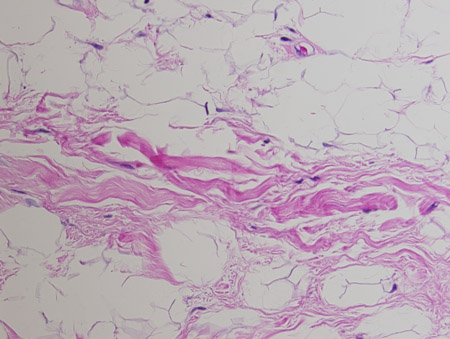

[Figure caption and citation for the preceding image starts]: Spindle cell lipoma. Mature adipose tissue with intervening strands of dense fibrosis with spindle cell areas and characteristic ropey collagen bundles. Haematoxylin and eosin, 200x magnificationFrom the collection of Dr Kimberly Moore Dalal and Dr Steven D. DeMartini; used with permission [Citation ends].

Spindle cell lipomas, often seen in men between the ages of 45 and 65 years, occur in the posterior neck and shoulder area.[16] They are characterised by mature fat being replaced by collagen-forming spindle cells.[17][18]